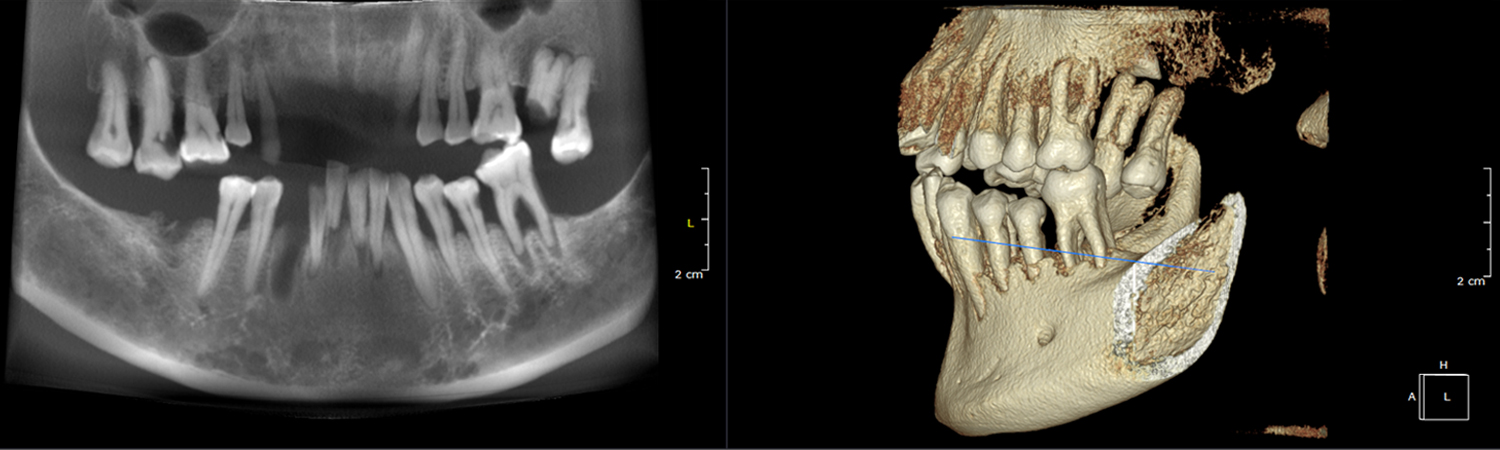

This technology provides highly accurate 3D radiographic images for the diagnosis, planning and treatment of dental implantology, TMJ analysis, airway assessment, oral and orthognathic surgery and other dental procedures.

Undistorted, anatomically correct views of the jaws, teeth and facial bones along with cross-sectional (bucco-lingual), axial, coronal, sagittal, cephalometric and panoramic views are easily generated.